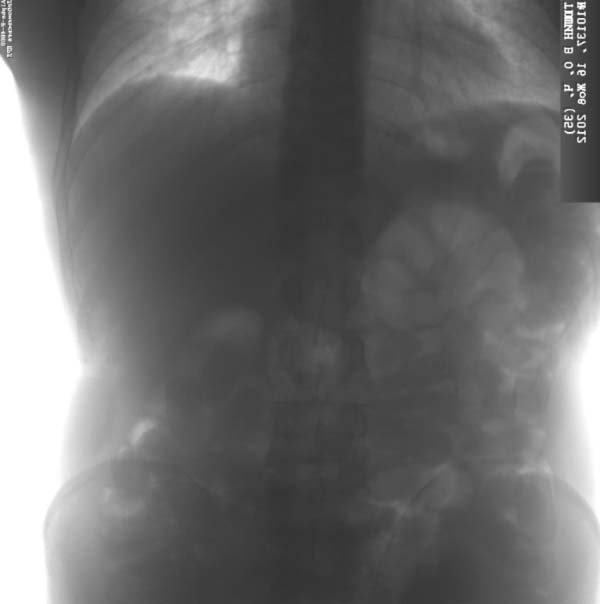

Кокаїн був розфасований у 34 капсули, які злочинець напередодні проковтнув. Капсули виявили в результаті рентгенографії у медичній установі.